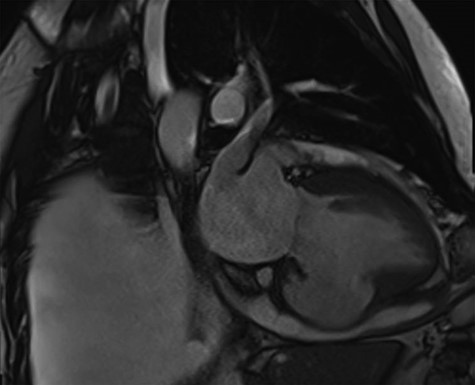

Pre-operative transthoracic echocardiogram (TTE) demonstrated both the left and right ventricles were dilated. Left ventricular (LV) function was mildly reduced, whereas right ventricular (RV) function was severely impaired. A large aneurysm was noted alongside a post-infarction VSD with left to right shunting (Fig. 1). Moderate MR was reported.

A pre-operative still from a TTE demonstrating a large VSD and a large RV aneurysm.